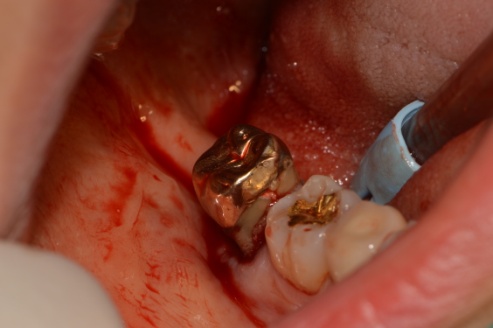

재식 _중 사진

다소 혐오스러울 수 있지만 건강하게 치아의 손상 없이 재식할 치아를 발치합니다.

건강하게 뽑은 치아

위 사진은 건강하게 발치된 치아입니다. 치아재식은 잇몸뼈와 치아 뿌리 부분의 치주인대가 건강해야 진행이 가능합니다.